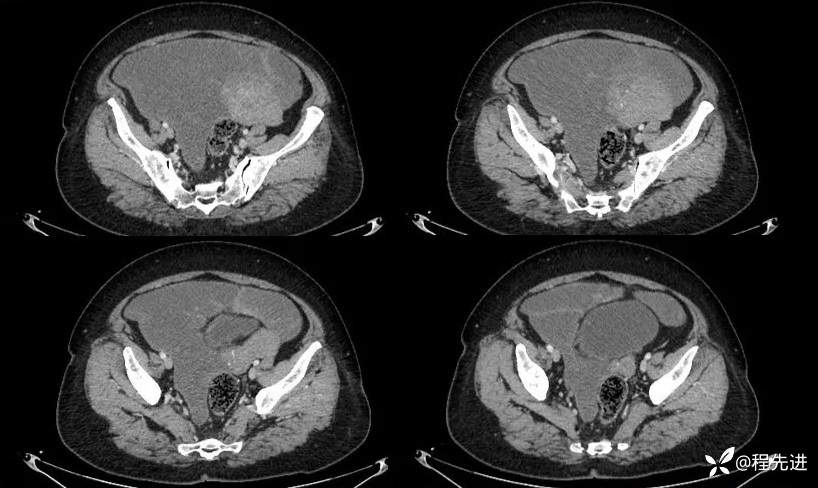

平扫:

延迟期: